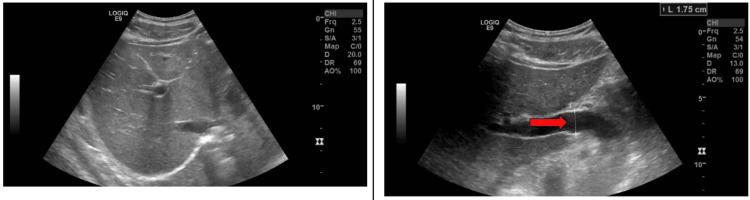

Selective androgen receptor modulators (SARMs) causing drug-induced liver injury is a rare, albeit inadequately described, potentially serious side effect for those in the fitness industry looking to maximize muscle growth, strength gain, and fat loss as quickly as possible. We present a case of a patient with drug-induced liver injury after starting Stenabolic, a newer SARM. We report a case of a 40-year-old male who presented with vague gastrointestinal symptoms. Before the presentation, he was relatively healthy but taking multiple over-the-counter supplements. Although he had been taking most of these supplements for a long time without notable side effects, he had recently started taking Stenabolic, a performance-enhancing drug under the SARM category. Laboratory and imaging studies confirmed hepatocellular injury. After ruling out infectious and autoimmune etiology, it was thought that the likely source was Stenabolic. The patient was treated with supportive care and was advised to discontinue Stenabolic. Upon discharge, he began to show clinical improvement. Although there is limited research about Stenabolic, other agents in the SARM class have been implicated in similar patterns of liver injury. Its structural and pharmacologic similarities to anabolic steroids raise concern for hepatotoxicity through an idiosyncratic immune-mediated mechanism. This case highlights the potential hepatotoxicity of performance-enhancing supplements like Stenabolic. With the growing popularity of SARMs and limited regulation, healthcare providers should maintain a high index of suspicion for supplement-induced liver injury. Further research is needed to clarify the safety and mechanisms of these agents. Until then, their use should be discouraged.

对于健身行业中希望尽快最大化肌肉增长、增强力量和减少脂肪的人来说,选择性雄激素受体调节剂(SARMs)导致药物性肝损伤是一种罕见但描述不足的潜在严重副作用。我们报告一例患者在开始使用新型SARM药物司腾勃龙(Stenabolic)后出现药物性肝损伤的病例。我们报告一名40岁男性,出现模糊的胃肠道症状。就诊前,他相对健康,但正在服用多种非处方补充剂。尽管他长期服用其中大部分补充剂且无明显副作用,但他最近开始服用司腾勃龙,这是一种属于SARM类别的增强运动表现的药物。实验室和影像学检查证实为肝细胞损伤。在排除感染性和自身免疫性病因后,认为可能的病因是司腾勃龙。患者接受了支持性治疗,并被建议停用司腾勃龙。出院时,他开始显示出临床改善。尽管关于司腾勃龙的研究有限,但SARM类中的其他药物也与类似的肝损伤模式有关。它与合成代谢类固醇在结构和药理上的相似性引发了对通过特异质免疫介导机制导致肝毒性的担忧。该病例突出了司腾勃龙等增强运动表现补充剂的潜在肝毒性。随着SARM的日益普及和监管有限,医疗保健提供者应高度怀疑补充剂引起的肝损伤。需要进一步研究以阐明这些药物的安全性和作用机制。在此之前,应不鼓励使用它们。